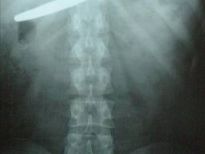

Çin'de yaşayan bu yaşlı adamın karısından çektiğini hiçbir erkek çekmemiştir herhalde. 66 yaşındaki Lin'in eşi, kumar ve alkol alışkanlığından şikayet edip duruyordu. Bir gün adam çok alkollüyken kafasına çivi bile çaktı.